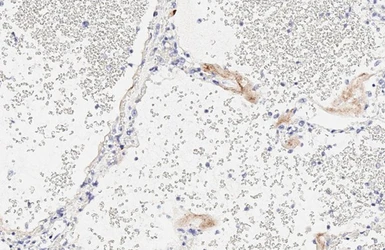

Anti-SARS-CoV-2 (COVID-19) Spike S1 antibody [HL6] used in IHC (Paraffin sections) (IHC-P). GTX635654

GTX635654 IHC-P Image

SARS-CoV-2 (COVID-19) Spike S1 antibody [HL6] (GTX635654) detects SARS-CoV-2 (COVID-19) Spike S1 protein by immunohistochemical analysis of SARS-CoV-2 infected human lung.

The IHC-P was performed by HISTOWIZ.